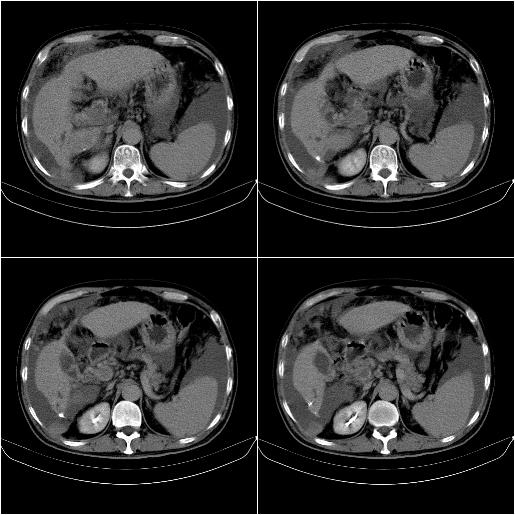

标题: CT21651:M,67Y,肝癌9月,介入术后3月。

m,67y,肝癌9月,介入术后3月。现腹胀、纳差、腹泻。

门静脉有很大的瘤栓,膈肌及膜膜有转移,不用再做了.

情况不好,门静脉癌栓、腹膜转移。

1)肝癌介入治疗术后碘油沉积不良。2)门静脉瘤栓形成,腹膜广泛性转移。3)肝硬化,脾大,腹水。4)慢性胆囊炎。